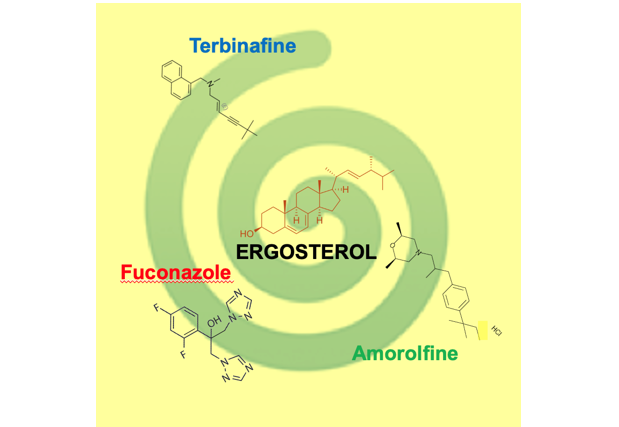

有機化学・薬学 同一経路で働く抗真菌剤の異なる作用~抗真菌剤の新しい用途開発に期待~

2024-08-06 東京大学発表のポイント◆テルビナフィン(TBF)、フルコナゾール(FCZ)、アモロルフィン(AMF)は真菌(カビや酵母など)のエルゴステロール合成を阻害する抗真菌剤ですが、これら3つの阻害剤が出芽酵母の形態に異なる影響...